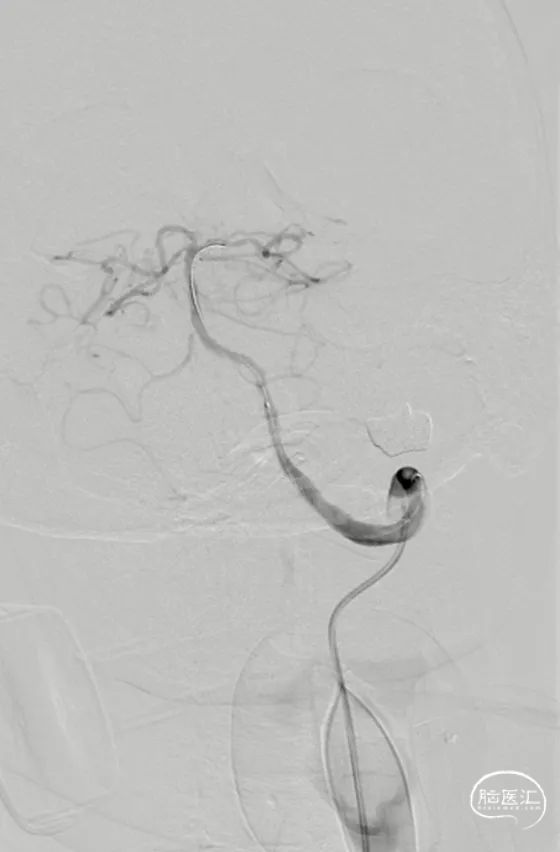

Tethys®中间导引导管沿导丝顺利到达病变近端附近,锁骨下至椎动脉转弯处充分体现了近端良好的⽀撑性与抗折性,帮助后续⾎管开通治疗建⽴稳定通路系统

中间导管到位后造影

微导丝通过狭窄段

微导丝置于左侧大脑后